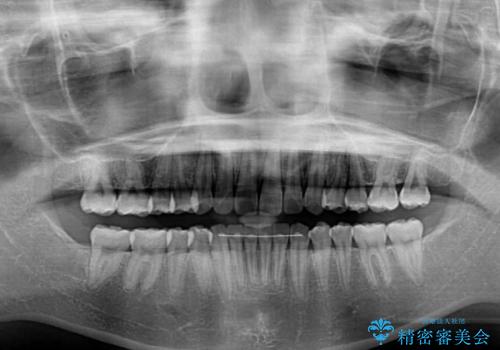

どこまで口元を引っ込めることができるのか、患者様自身も正直分からない部分があったため、少しずつ治療ゴールを変更しながら仕上げていきました。

気になっていた前歯の飛び出した印象は、最終的にはスッキリと引っ込み、大変満足していただきました。